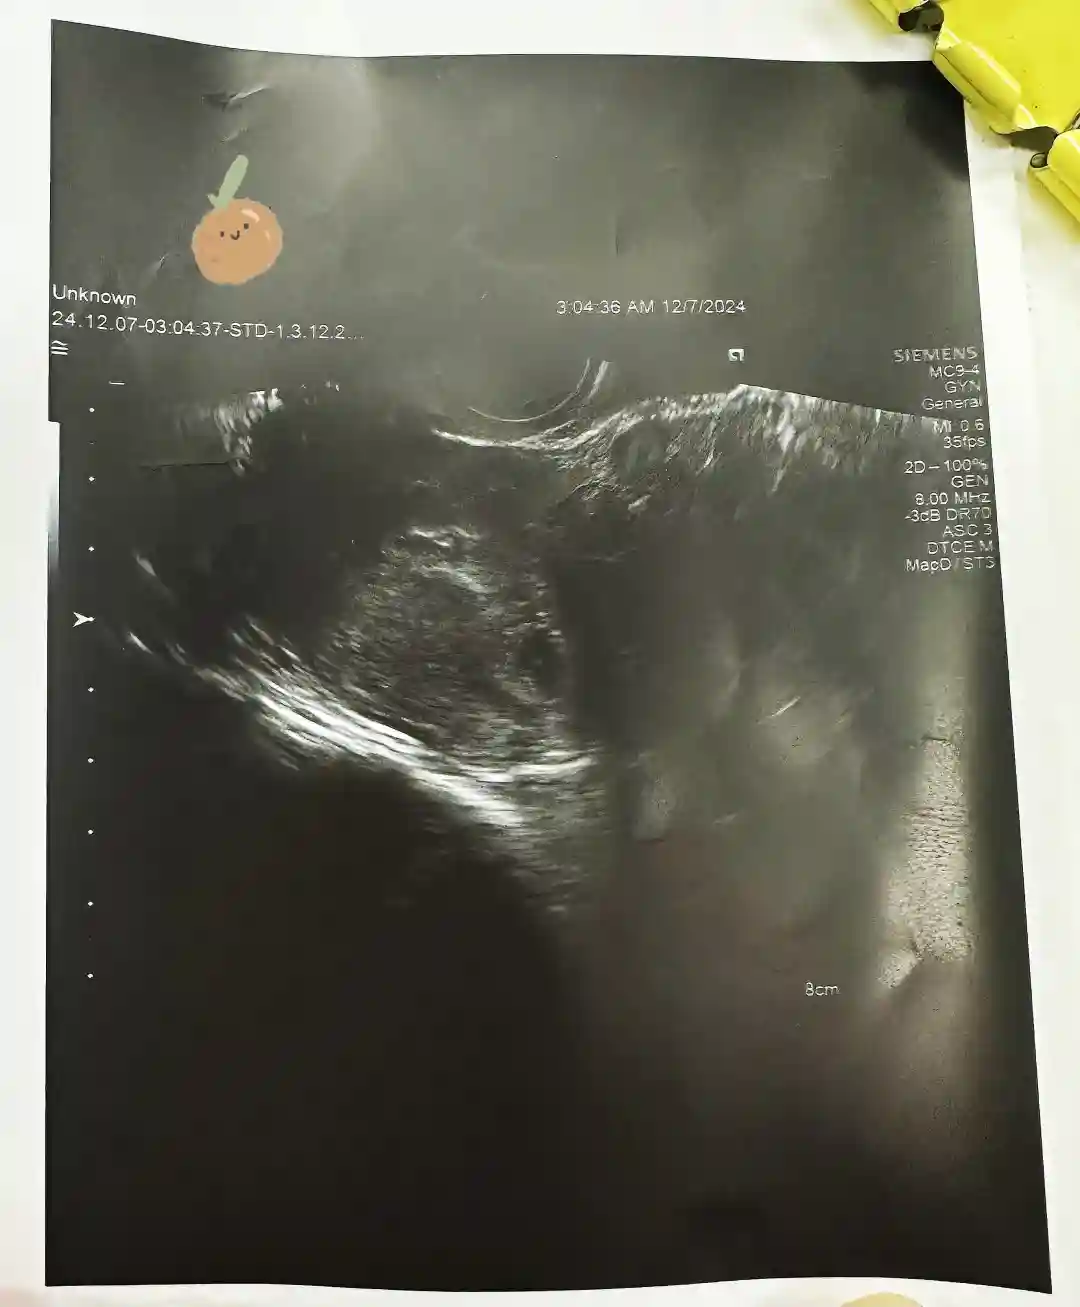

11月进行了三移,移植当天洪医生第一个进手术间,她手脚很快,也很仔细。移后三天我就出血了,吓得我心都凉了,不抱希望地大卫一测,灰印,但联想到上次生化的经历并没有太开心。立马联系了洪医生,她马上喊我去抽血,看翻倍,加药,就这样一路磕磕碰碰,终于五周多做了一超,看到了小豆芽的雏形。